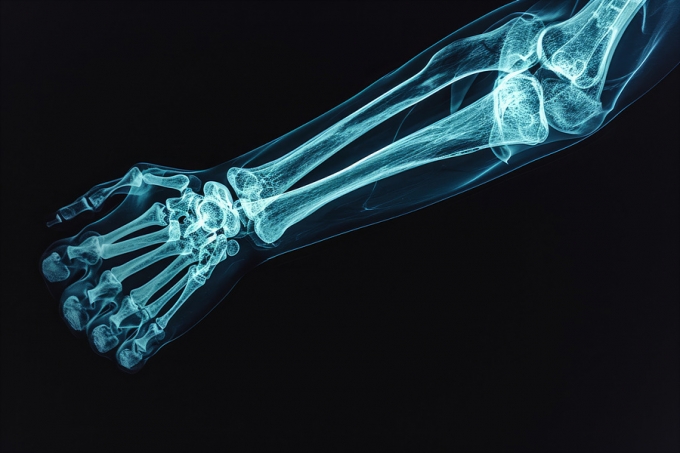

결과는 충격적이었다. PFAS 대표 물질인 과불화옥탄산(PFOA) 농도가 높은 청소년일수록 팔뚝 골밀도가 낮은 경향이 확인됐다. 일반적인 골밀도를 100으로 두면 PFOA 노출이 높을수록 골밀도가 98~92 수준까지 떨어지는 것으로 확인됐다. 연구팀은 "골밀도가 90만 되어도 골절 위험이 약 1.4배 증가한다"고 설명했다.

버클리 교수는 "청소년기는 평생 뼈 건강을 좌우하는 골량을 형성하는 핵심 시기"라며 "이 시기에 충분한 골밀도를 확보하지 못하면 향후 골절이나 골다공증 위험이 높아질 수 있다"고 경고했다. 이어 "이번 연구를 통해 식수와 식품 포장재, 생활용품 등 일상생활 속 PFAS 노출을 줄이기 위한 관리가 필요하다는 사실이 드러났다"면서 "PFAS 규제에 대한 보건학적 근거가 될 수 있겠다"고 덧붙였다.